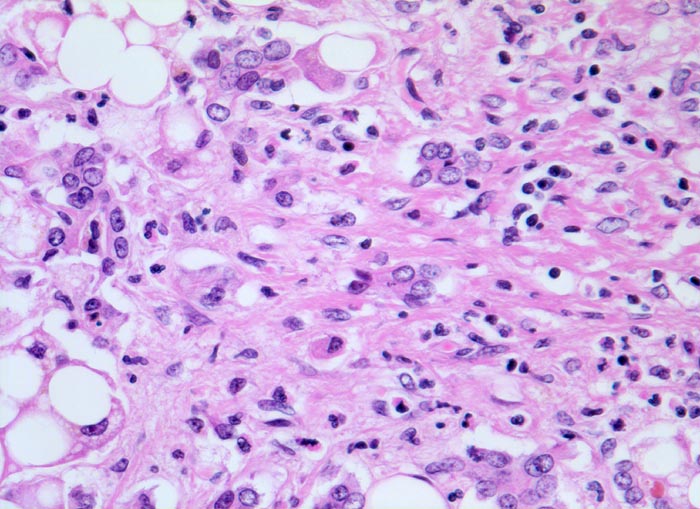

alkoholische Leberzirrhose, Portalfeld

Fibrös verbreitertes Portalfeld mit proliferierten Ductuli und lockerem gemischtem Entzündungsinfiltrat. Grobtropfig verfettete Hepatozyten.

Breite bindegewebige Septen und Ductulusproliferationen sind typisch für die alkoholische Leberzirrhose.